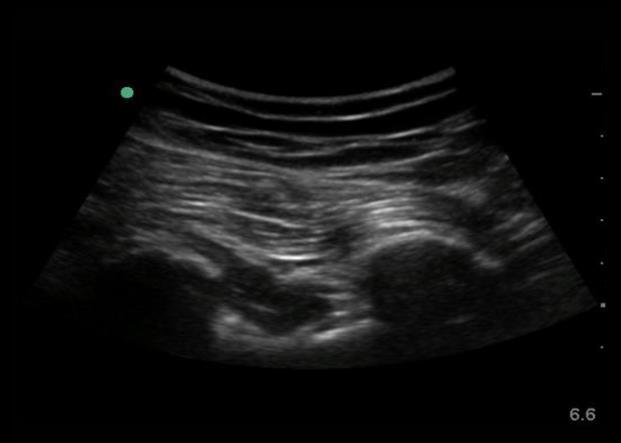

Imagen del nervio ciático y de los músculos glúteos mayores en la parte posterior de la cadera